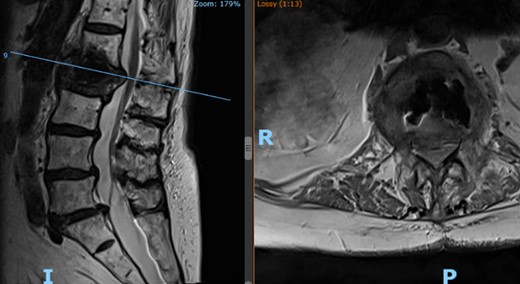

The patient is an 82-year-old female with a history of hypertension and osteoporosis with BMI of 34.39. The patient presented with worsening, 10/10 lower back pain for the past 3 weeks, which interfered with her ability to perform activities of daily living (ADLs). Her pain started in the midline lumbar spine, radiating laterally across her back into her buttocks and bilateral groin. MRI with no contrast of the lumbar spine revealed L2 compression fracture with concurrent injury to the L1-L2 disk (Fig. 1). The patient was referred to interventional radiology (IR) for L2 kyphoplasty.

Preoperative lateral (left) and axial (right) MRI of the patient’s spine showing L2 compression fracture.